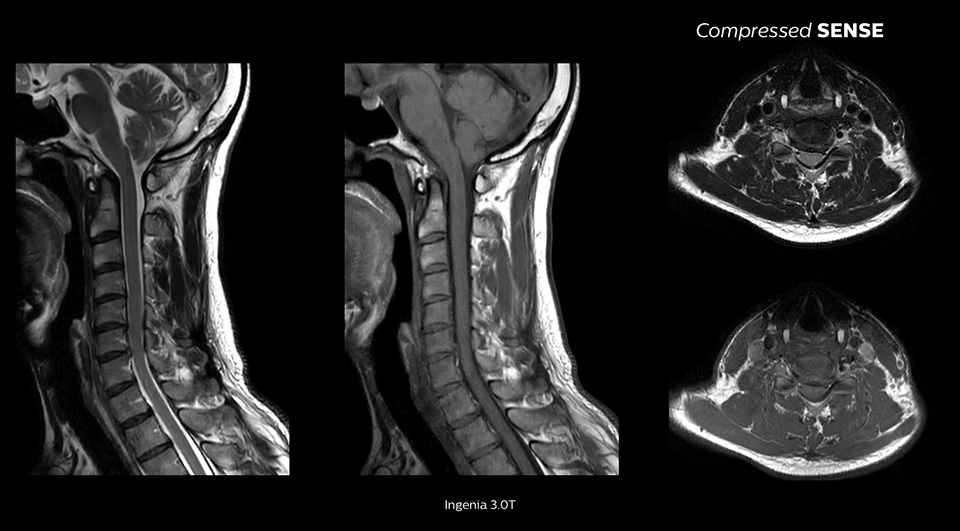

当施設では、ルーチンプロトコルにCompressed SENSEを使用し、検査時間を20%短縮させています。読影時では、Compressed SENSEを使用したのかどうか区別することができないくらい画質の変化はありません」

John P. Karis医師、MRIおよび脳撮像ディレクター、Department of Neuroradiology at Barrow Neurological Institute、米国

画質は同等のまま高速化が可能1

空間分解能が最大64%向上1